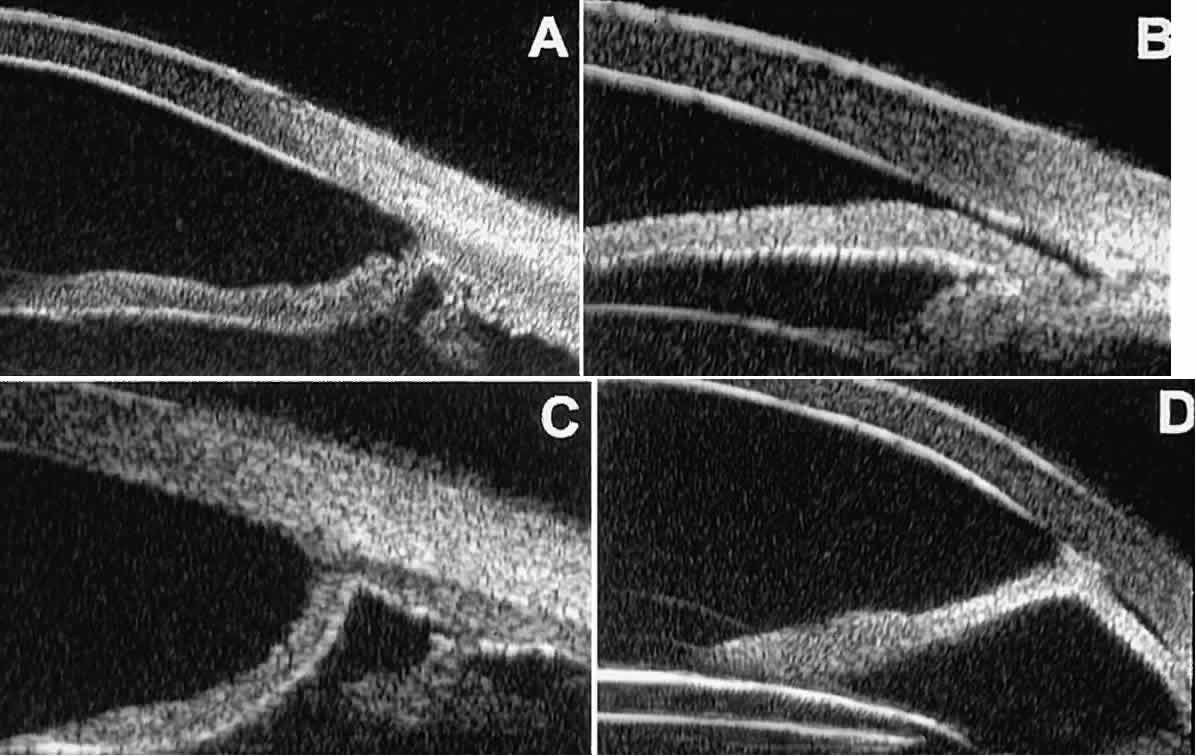

In open-angle glaucoma, UBM can be used to measure the anterior chamber angle in degrees, to assess the configuration of the peripheral iris, and to evaluate the trabecular meshwork (Fig. 9).2,4 The angle configuration can be graded and compared with gonioscopic findings. In certain patients with open-angle glaucoma, UBM can provide information that may be of some diagnostic value (Fig. 10). For example, in pigment dispersion syndrome (see Fig. 10A),6 UBM typically reveals posterior bowing of the peripheral iris (“q” configuration of peripheral iris by Spaeth classification5). In plateau iris syndrome (see Fig. 10B),7 UBM usually reveals abnormally steep anterior angulation of the peripheral iris (“s”configuration of peripheral iris by Spaeth classification5), insertion of the iris from the anterior ciliary body, and retroiridic projection of the ciliary processes. In eyes with peripheral anterior synechiae (see Fig. 10C and D), UBM can reveal the extent of iridocorneal adhesion even if the cornea is hazy or opaque.

Fig. 9. Angle configuration in eyes with open-angle glaucoma. A. Wide open angle with flat iris plane (D40r configuration by Spaeth gonioscopic grading system). B. Moderately wide angle with anteriorly bowed iris plane (C30r by Spaeth gonioscopic grading system).

Fig. 10. UBM features of special glaucoma cases. A. Pigment dispersion syndrome with posterior bowing of peripheral iris (“q” configuration by Spaeth gonioscopic grading system). B. Plateau iris syndrome with origin of iris from anterior surface of ciliary processes behind peripheral iris, slitlike narrowing of peripheral angle, and abrupt transition from steep peripheral iris to flat iris midzone. C. Broad peripheral anterior synechia with posterior bowing of nonadherent iris. D. Peripheral anterior synechia with aqueous-filled slit between site of iridocorneal adhesion and iris root after cataract extraction with implantation of posterior-chamber IOL.

In eyes with a narrow angle, UBM shows the extent of angle closure, reveals the depth of the anterior and posterior chambers, and identifies pathologic processes pushing the lens and iris forward (Fig. 11).2–4,8 UBM has been able to differentiate between primary angle closure (i.e., cases of angle closure without additional pathology responsible for the anterior lens-iris displacement [see Fig. 11A] and secondary angle closure due to processes such as lens swelling and dislocation (see Fig. 11B), massive hemorrhagic retinal detachment pushing the lens and iris anteriorly (see Fig. 11C), and multiple neuroepithelial cysts of the iridociliary sulcus (see Fig. 11D).

Fig. 11. Angle configuration in eyes with angle-closure glaucoma. A. Primary angle-closure glaucoma with anterior displacement of lens and iris. B. Angle closure secondary to swollen, cataractous lens (phakomorphic angle closure). C. Angle closure secondary to massive hemorrhagic retinal detachment; the subretinal blood is evident in the lower right corner of the photograph. D. Angle closure secondary to multiple peripheral iris cysts.